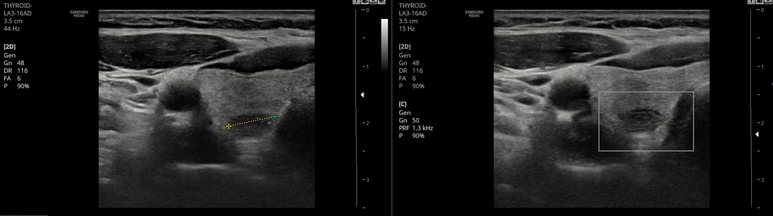

위치를 보았을때 새열 낭종을 배제위해 초음파 시행

10 mm를 초과하는 림프절들이 area III~II, SCM 위쪽에 2개 관찰; hilum의 지방 구조가 관찰되나 둥그렇고 켜져있다.

경동맥, 경정맥 외측으로 작은 림프절이 다수; hilum의 지방 구조가 관찰되지 않는다.

낭종이 아님을 확인하였고,

1주일 전부터의 증상이라 염증성 혹은 반응성을 고려하였으나 임상적으로 발열이나 인후통등은 선행하지 않았다. kikuchi 등 감별질환에 대해 설명하고 (절제생검 까지 가능성도 고려하여) 의뢰하였다.

그러나, 갑상선의 동반된 결절을 생각하면 갑상선 및 림프절의 세침검사를 먼저 시행해 볼 수도 있겠다.